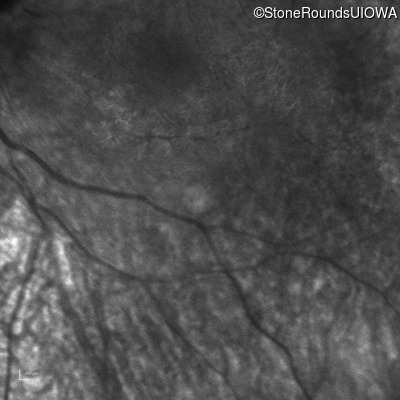

Infrared Fundus Photograph - Right -

No Light Perception

Exemplar

Infrared Fundus Photograph - Left -